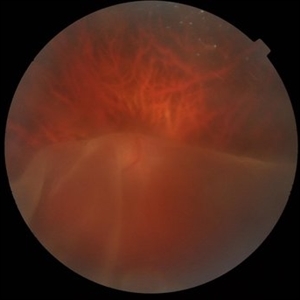

SUNSET THROUGH A VEIL

Oct 12 2023 by Deepti A Kulkarni, M.B.B.S., D.N.B., F.V.R.

HIGH MYOPE WITH A CORRECTION OF -24D. SUDDEN VISION LOSS FOLLOWING TRAUMA. SUPERIOR RETINA FOLDED ON TO THE INFERIOR RETINA MASKING THE DISC IN A TRANSLUCENT VEIL.

Photographer: DEEPTI KULKARNI, DR ANIL KULKARNI EYE HOSPITAL, MIRAJ, INDIA

Imaging device: TOPCON

Condition/keywords: GIANT RETINAL TEAR